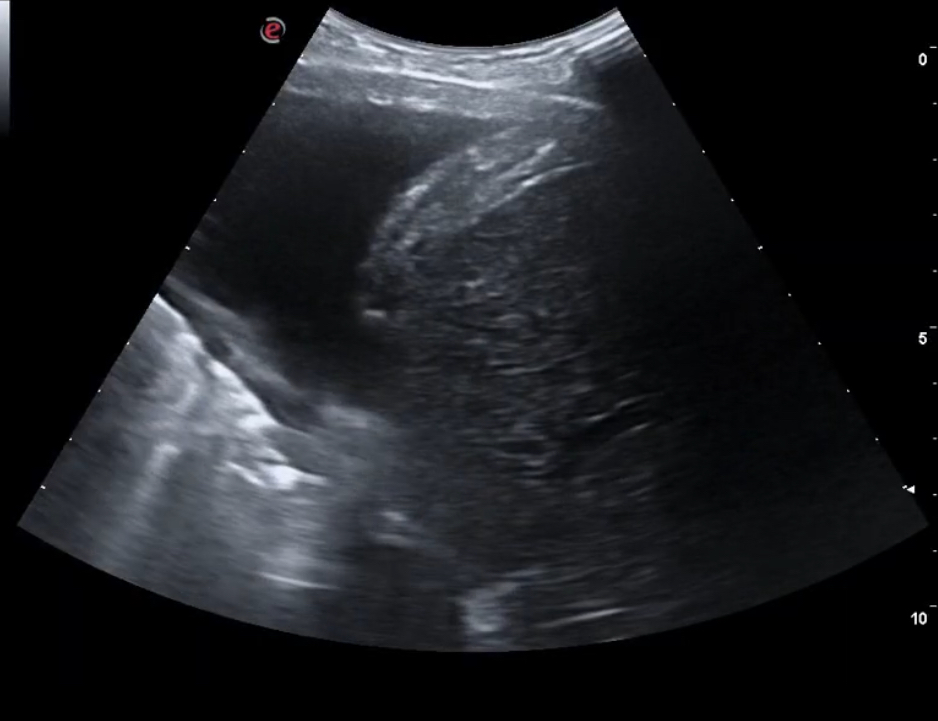

Para cuantificar el grado de insuficiencia cardíaca, además de la exploración cardiorrespiratoria y de miembros inferiores, la ecografía clínica pulmonar nos permitiría valorar, en los 18 campos, la presencia de líquido pleural, con la distorsión por aparición de mayor a tres líneas B, además de la valoración de líquido en senos costofrénicos.

La ecografía pulmonar nos evita utilizar técnicas más invasivas y los ingresos tardíos hospitalarios para un control de la insuficiencia cardíaca, que se puede controlar en Atención Primaria utilizando el tratamiento adecuado precoz, y monitorizando la evolución con la ecografía.